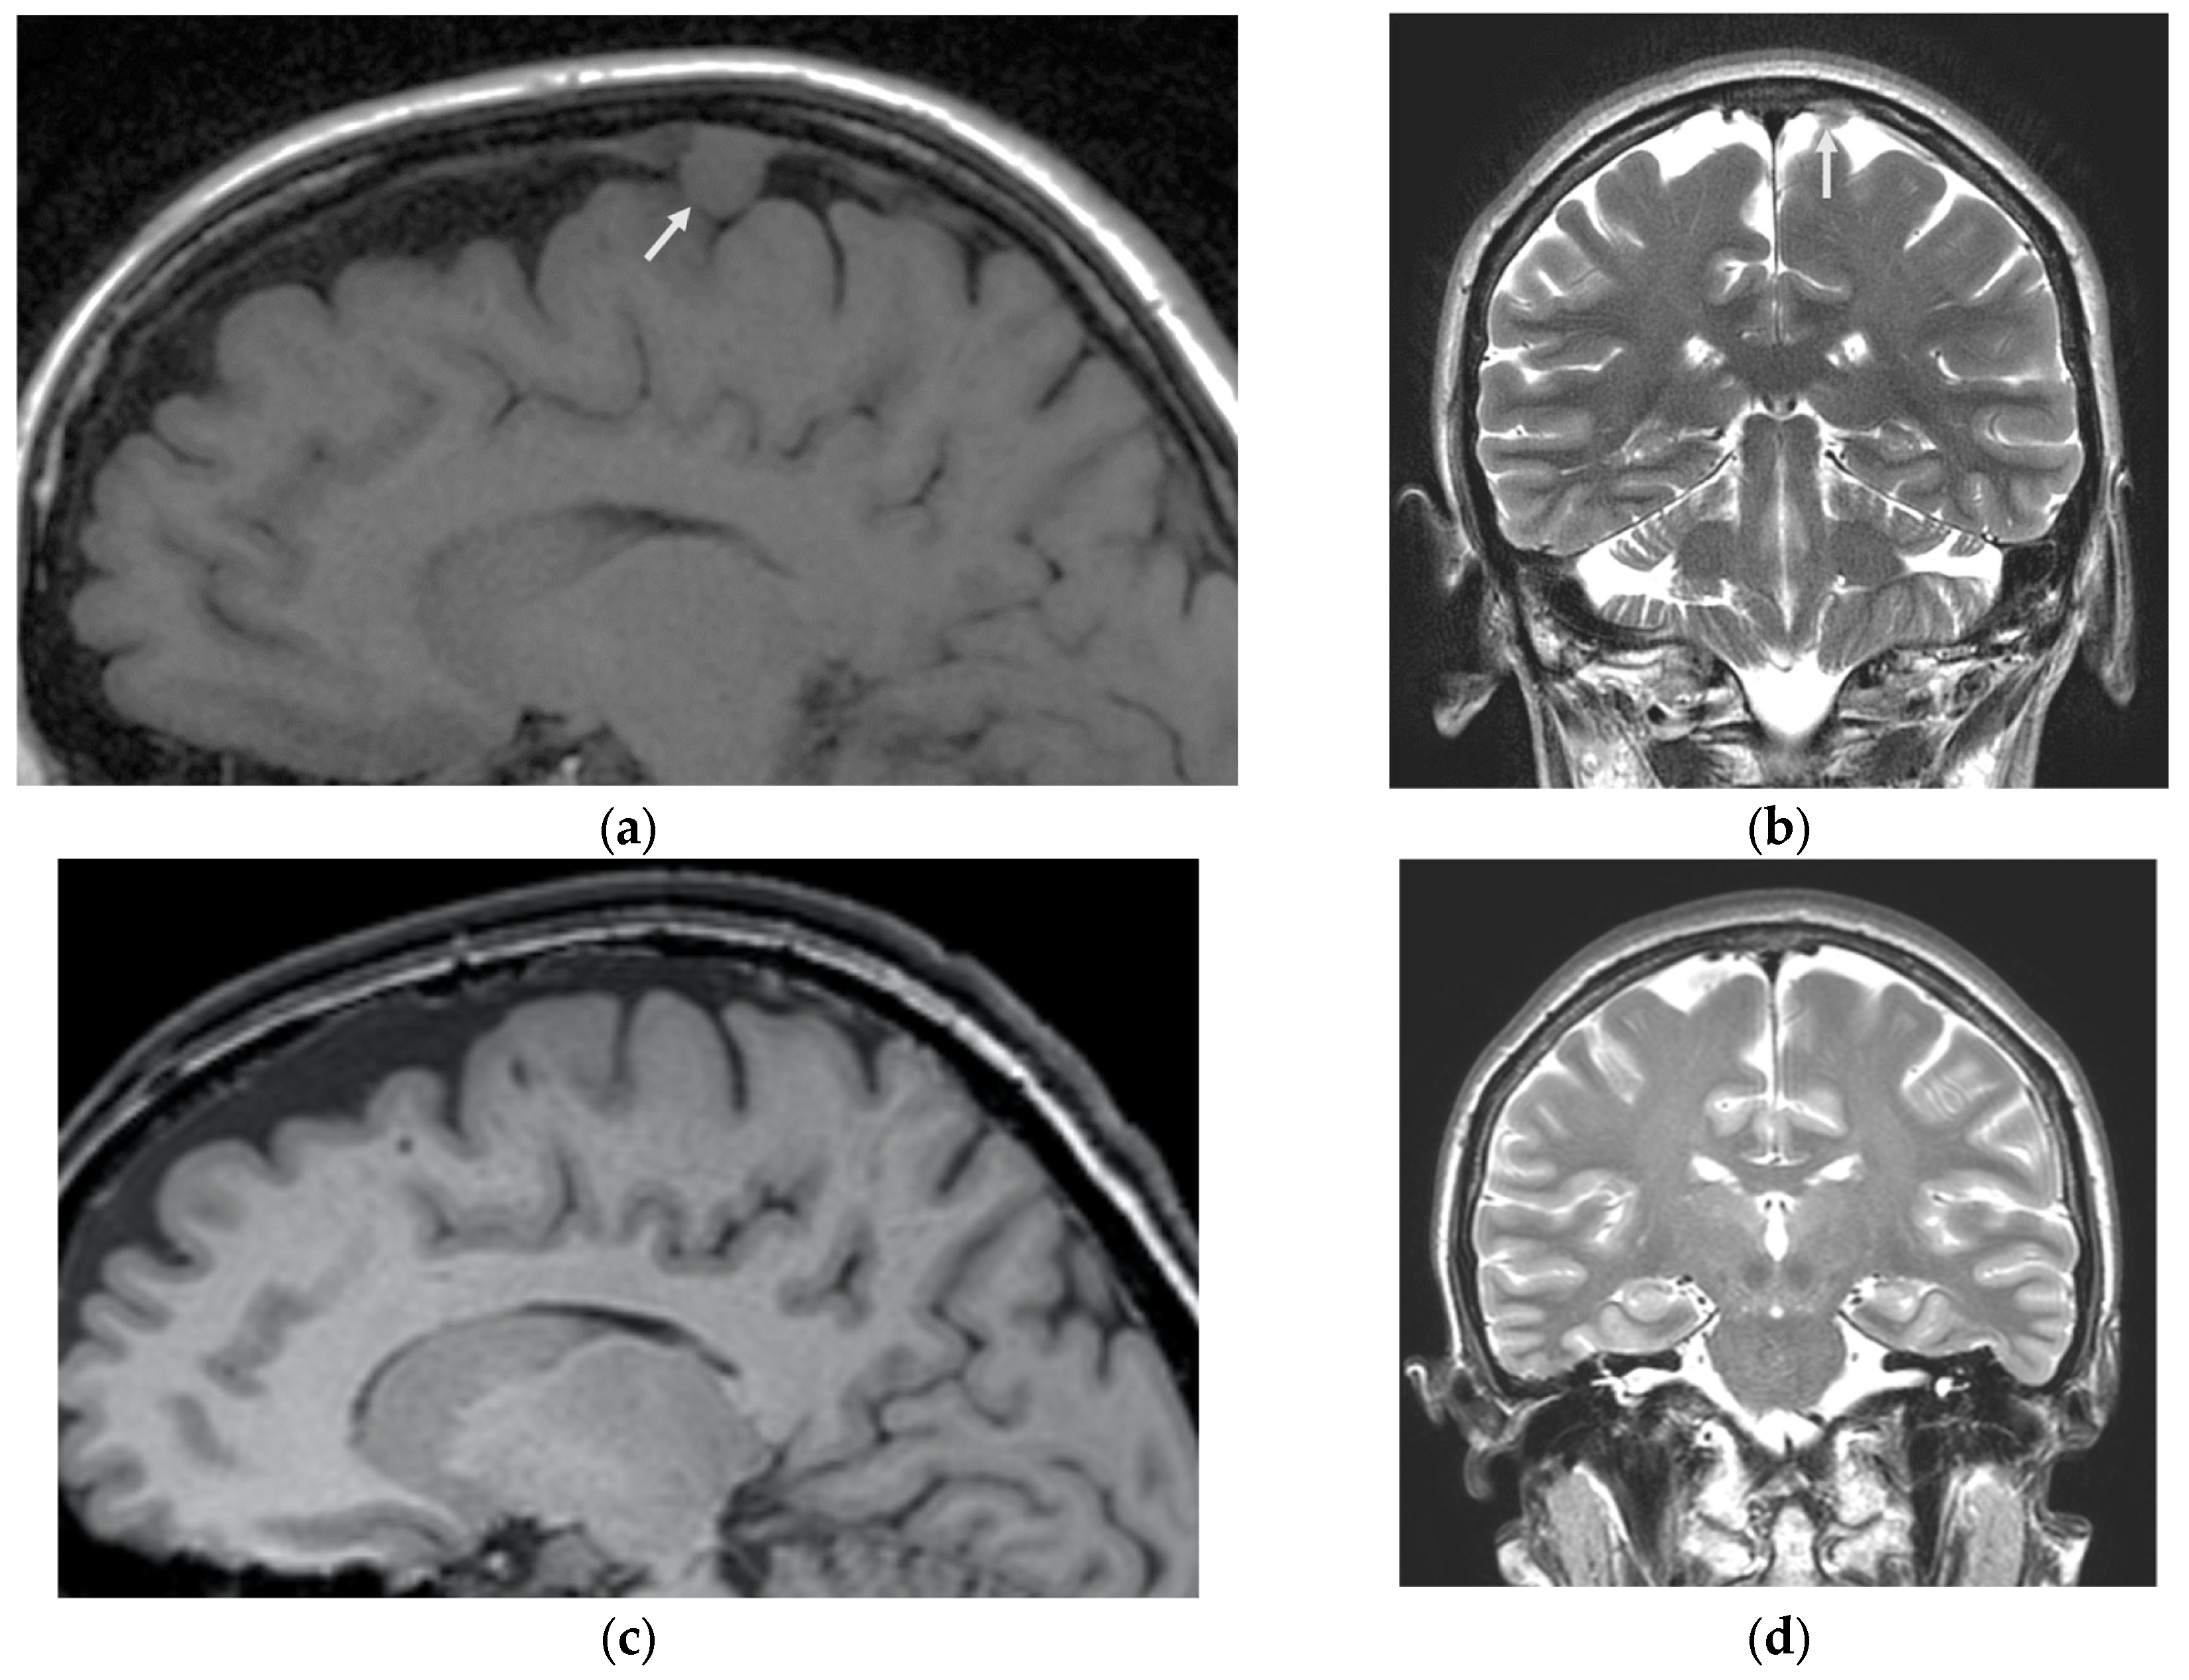

2.1. Meningioma Embolisation

Under general anesthesia, a right femoral transarterial approach was performed. A 7F introducer was inserted, and 2.5 milliliters of heparin solution was administered. Digital subtraction angiography (DSA) was then performed from the right and left internal carotid arteries, external carotid arteries, and the right vertebral artery to reveal the vascular network of the tumor in the left frontal region. Afferent vessels were found to originate from the frontal and parietal branches of the left middle meningeal artery (MMA)and also from collateral vessels from the opposite (right)MMA (Figure 2a,b). A 7 Fr Guide Softip guiding catheter (Boston Scientific) was inserted in to the left external carotid artery, and the frontal branch of the left MMA was catheterized distally using a Headway 17 microcatheter (MicroVention) with a guide wire Asahi Chikai 0.010-inch (Asahi Intecc). Figure 2c,d show DSA images obtained through the microcatheter. Embolization was performed using non-adhesive, minimally viscosity Squid 12 (Balt) material, with an injection volume of 0.6 mL. The distribution of the embolic agent after the initial injection is shown in Figure 2e,f. After achieving the limit of the embolic agent’s penetration into the tumor vascular system through this afferent pathway, the microcatheter was removed and the ipsilateral parietal branch of the MMA was catheterized, followed by DSA (Figure 2g,h). Partial contrast was observed in the remaining vascular network of the lesion from this afferent artery. The tip of the microcatheter was positioned as distally as possible along the ipsilateral parietal MMA. With this positioning, a second injection of Squid 12 (Balt) was administered, which extended well into collateral vessels, including the contralateral MMA. However, the injection was halted when the embolic material started to spread into dural veins and the injection volume was increased to 0.7 mL (Figure 2i,j). Then, the embolic agent with the lowest viscosity was substituted with a standard viscosity (Squid 18 (Balt)), which was administered in a volume of 0.4 mL. In the craniograms without subtraction, the embolized area is clearly visible, reproducing the afferent blood supply of the vascular network of the tumor (Figure 2k,l). Therefore, during the embolization procedure, the dura mater was extensively deprived of blood vessels on both the ipsilateral and contralateral sides.

Figure 2. Digital subtraction angiography (DSA) and craniograms showing the stages of endovascular embolization of middle meningeal artery (MMA) branches in a patient with a combination of parasagittal meningioma and chronic migraine: (a) lateral and (b) frontal DSA projections from the left MMA show the contrasting vascular network of the parasagittal meningioma in the left frontal region (indicated by the white arrow). The afferents from the frontal and parietal branches of the left MMA, as well as collateral vessels from the contralateral right MMA, are visible; (c) lateral and (d) frontal DSA images from a microcatheter placed in the frontal branch of the left MMA show the site of embolization; (e) lateral and (f) frontal DSA show the spread of a first push of a non-adhesive, minimally viscous embolic agent (Squid 12, Balt), with an injection volume of 0.6 ml.; (g) lateral and (h) frontal projections of DSA demonstrating the contrast between the remaining vascular network of the tumor and afferents from the ipsilateral parietal branch of the MMA; (i) lateral and (j) frontal DSA projections showing the spread of the initial Squid 12 (Balt) injection and its distribution across collaterals, including the contralateral MMA; Craniograms in (k) lateral and (l) frontal views demonstrating the radiopaque cast of non-adhesive embolic compositions of various viscosities (Squid 12/18, Balt) in both MMAs.